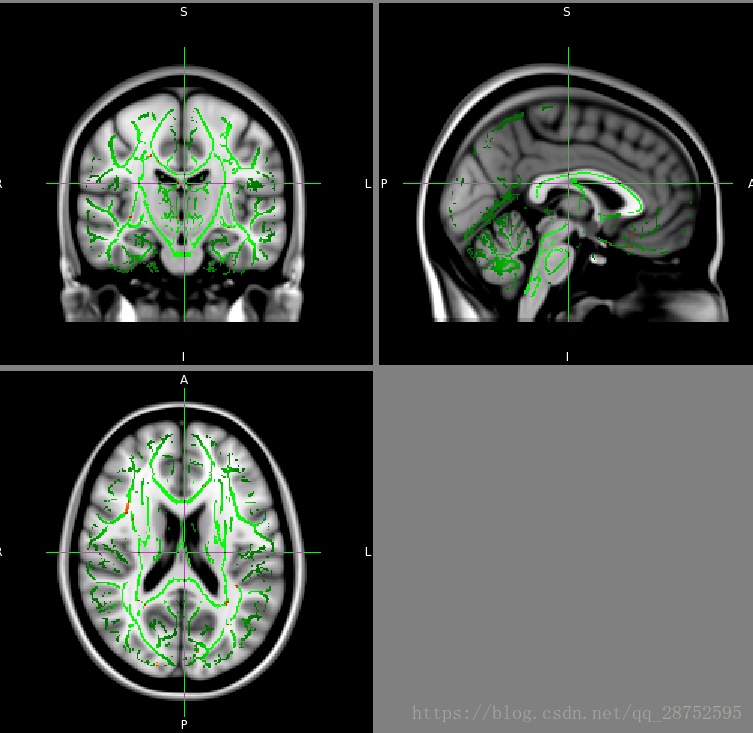

cd ../stats design_ttest2 design 34 48 randomise -i all_FA_skeletonised -o tbss -m mean_FA_skeleton_mask -d design.mat -t design.con -n 500 --T2 fslview_deprecated $FSLDIR/data/standard/MNI152_T1_1mm mean_FA_skeleton -l Green -b 0.2,0.8 tbss_tstat1 -l Red-Yellow -b 3,6 tbss_tstat2 -l Blue-Lightblue -b 3,6

在这种情况下,contrast 1给出对照>患者测试,contrast 2给出对照<患者测试。原始(非阈值)tstat图像分别为tbss_tstat1和tbss_tstat2。TFCE p值图像(对于跨空间的多次比较完全校正)是tbss_tfce_corrp_tstat1和tbss_tfce_corrp_tstat2(注意,为了便于显示,这些实际上是1-p,因此在.95处的阈值处理给出了重要的簇)。

显示TBSS结果

假设您希望在MNI152图像上显示结果,因此首先将MNI152加载到FSLView中。接下来,可能需要在背景图像上加载mean_FA_skeleton图像,以显示估计骨骼的位置,以及在多科目统计中测试哪些标准空间体素。加载mean_FA_skeleton在FSLView并正确地设置其显示范围。必须将下限阈值设置为您在TBSS分析中使用的阈值,例如0.2。上层应该设置为0.7,这样你就可以看到骨架内平均FA值的变化。您可能想要更改颜色图,例如更改为绿色,并增加透明度(使用透明度滑块),以便在加载统计图像时,更容易看到。最后,加载stats图像。如果你已经在随机中使用了基于TFCE的测试,那么原始t统计图像将被命名为类似于tbss_tstat1(你可以在显着性测试之前查看原始tstats),但你的图像可能是tbss_tfce_corrp_tstat1,这是经过校正的p值图像(实际上,为了便于显示,此图像中的值为1-p,因此更大的“更好”)。将其加载到FSLView中,设置颜色映射(如红黄色),并将显示范围设置为0.95:1,这对应于在p <0.05处对结果进行阈值处理。以上所有(除了设置骨架透明度,必须在GUI中手动完成)可以使用单个命令执行:

fslview_deprecated $FSLDIR/data/standard/MNI152_T1_1mm mean_FA_skeleton -l Green -b 0.2,0.7 tbss_tfce_corrp_tstat1 -l Red-Yellow -b 0.95,1